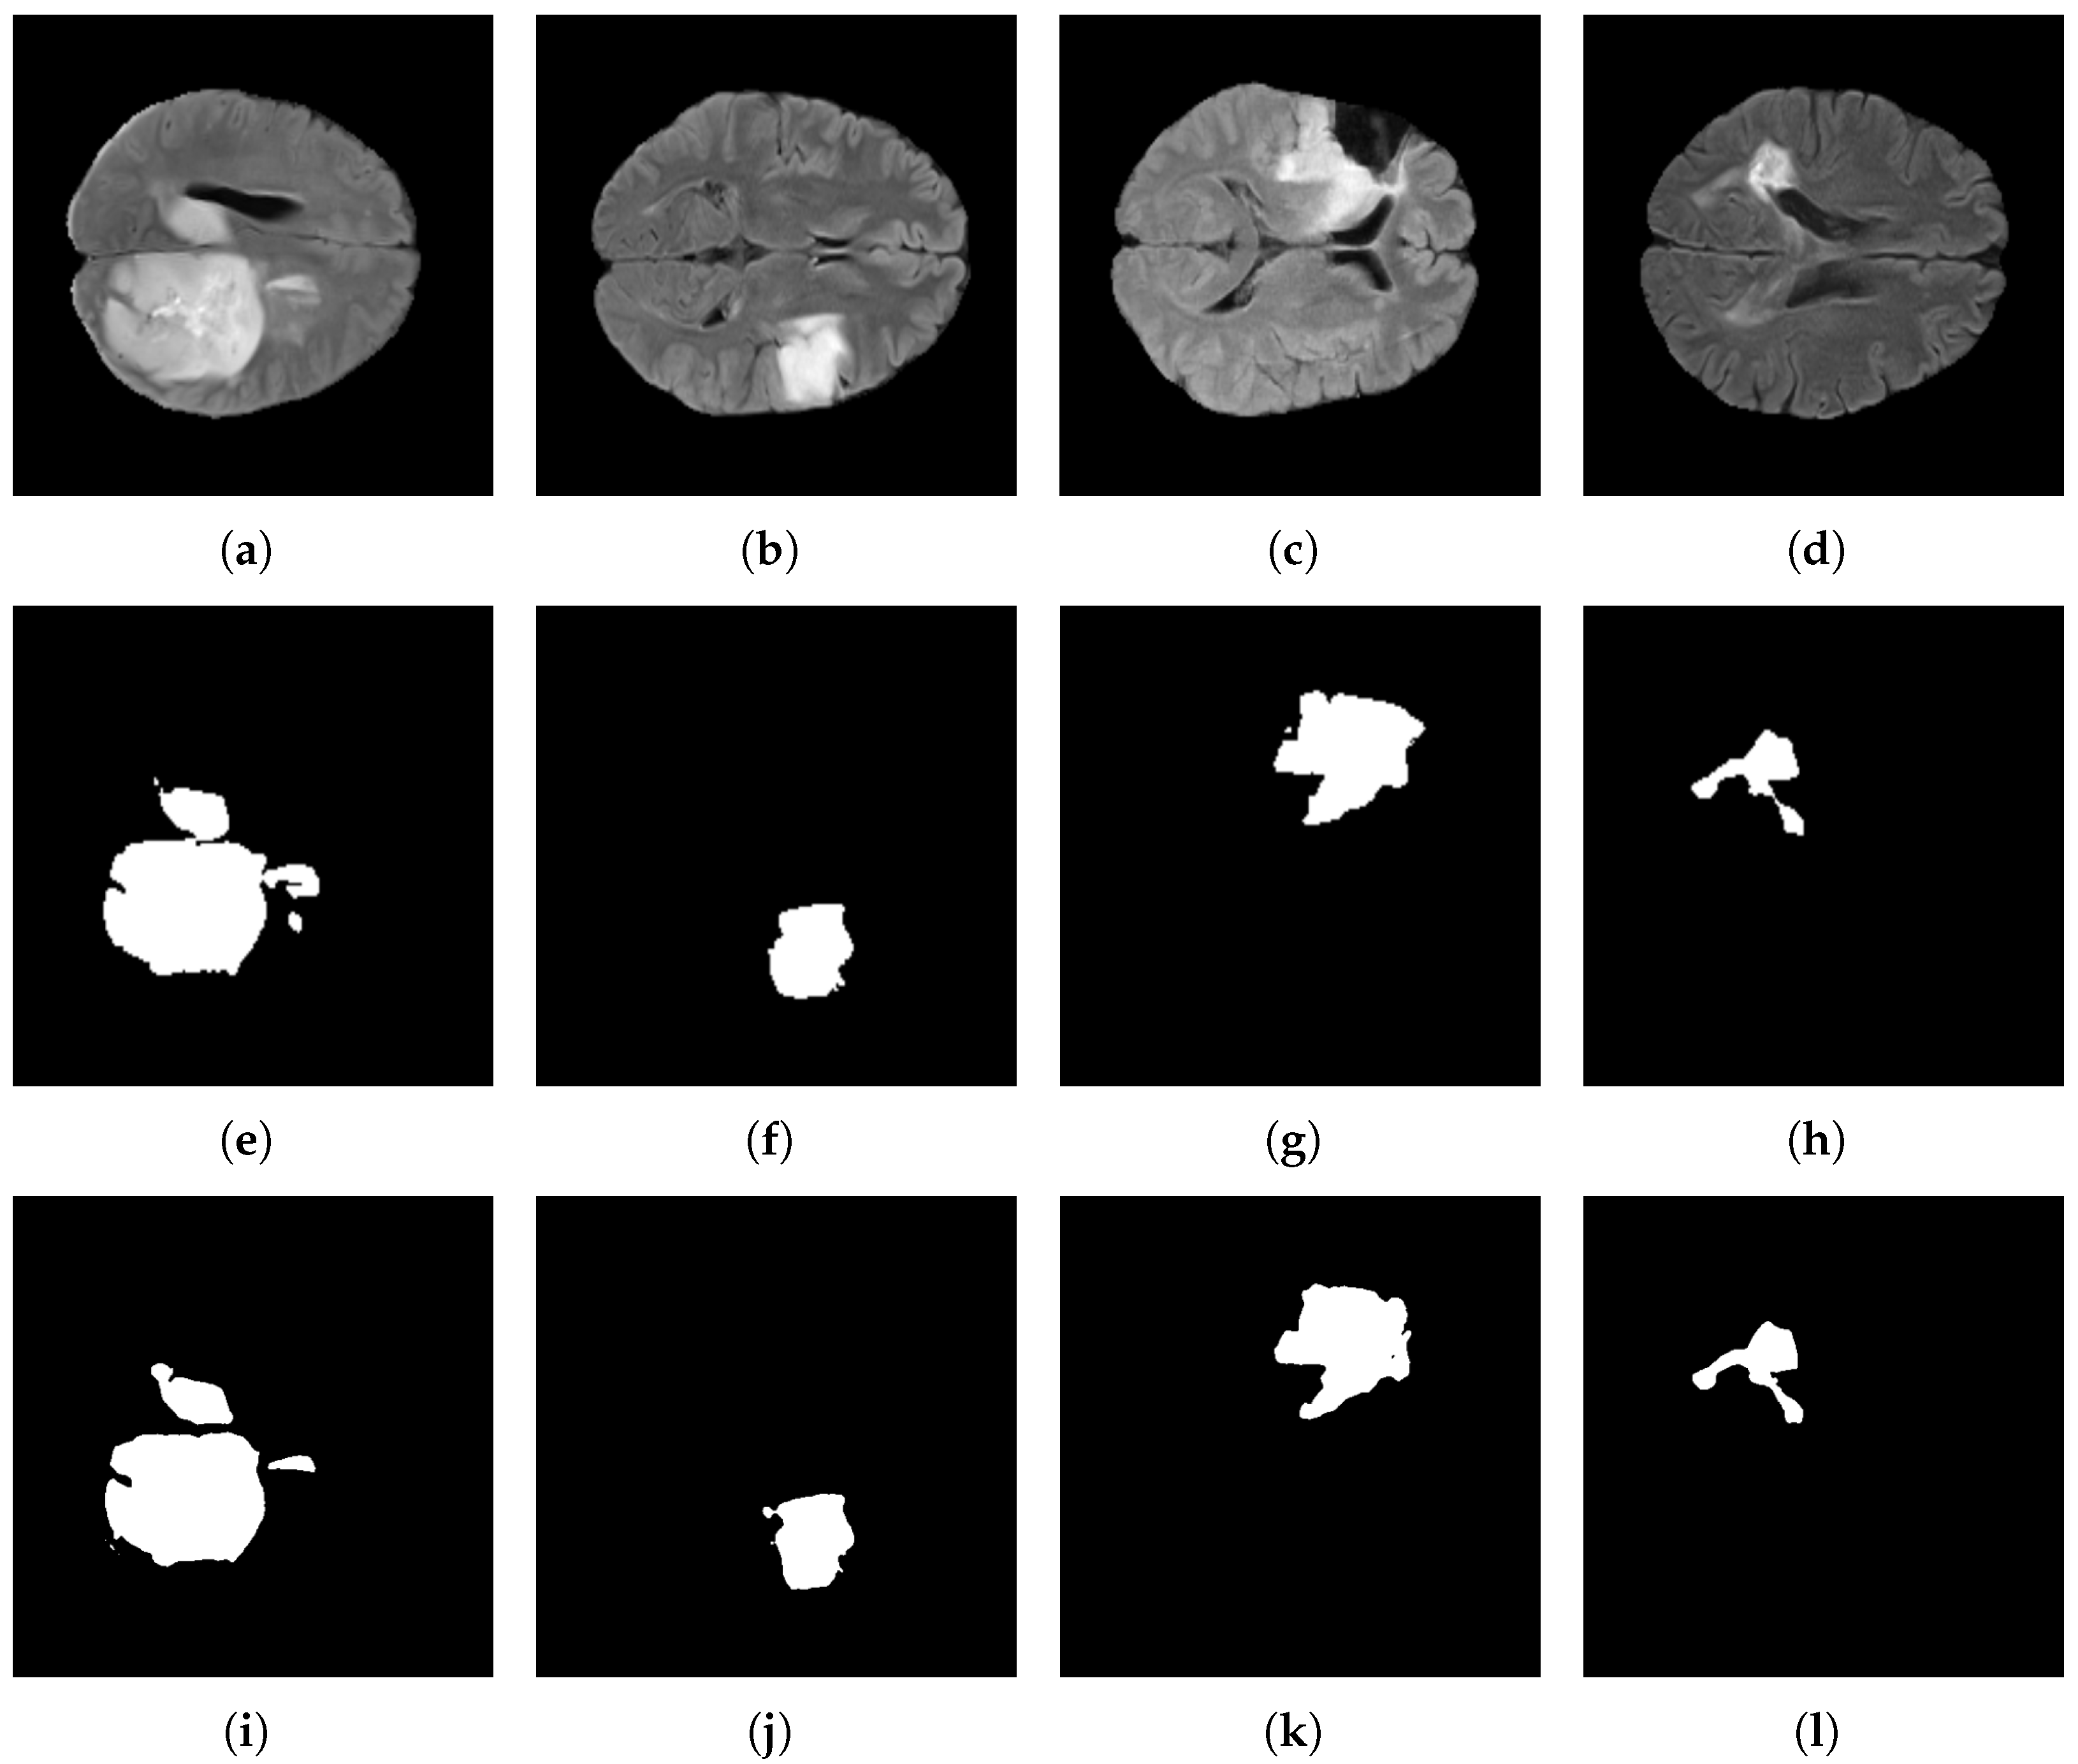

Figure 15 depicts the segmentation results for the BraTS 2021 dataset. The first row shows the original input images. The second row displays the corresponding ground-truth masks, while the third row illustrates the predictions generated by the proposed model.

Figure 15e shows a tumor with a rounded morphology; correspondingly, the model completely delineates it in Figure 15i, preserving a smooth boundary. By contrast, Figure 15f shows a spiculated contour with sharp protrusions, and the model accurately captures these border irregularities in Figure 15j without excessive smoothing effects. Finally, Figure 15h contains a small tumor; nevertheless, the model consistently localizes and segments it in Figure 15l, demonstrating sensitivity to small targets while limiting over-segmentation of adjacent tissues.